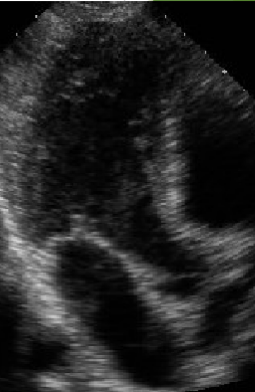

<p>What view is this?</p>

What view is this?

Apical 5 Chamber